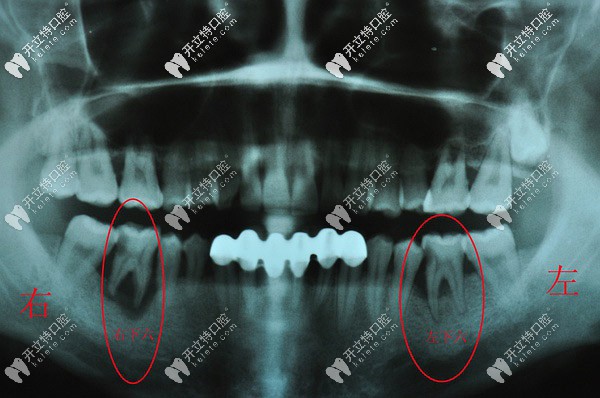

凸嘴齙牙正畸拔智齒推磨牙向后和拔4號(hào)牙哪個(gè)更好?

齙牙齒矯正拔牙牙齒正畸發(fā)布時(shí)間: 2025-04-29

凸嘴牙齒矯正你可能面臨以下兩周方案,拔智齒磨牙后推和拔4號(hào)牙哪個(gè)更好?